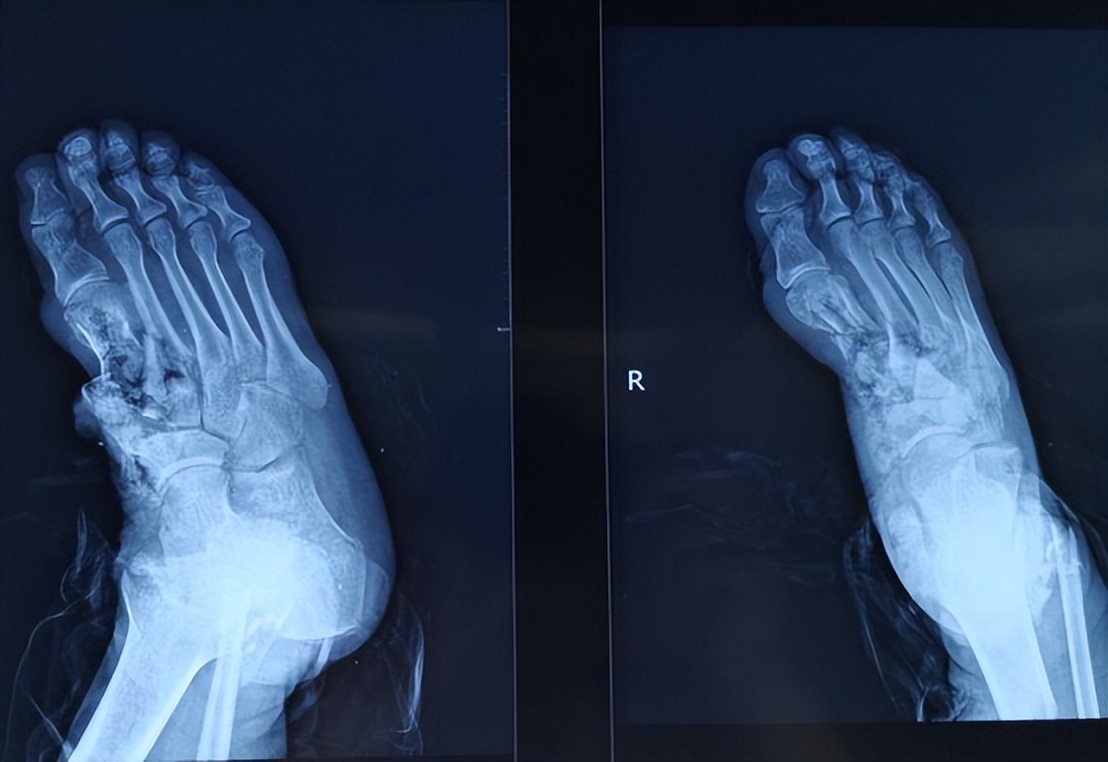

对于深度烧伤的创面,手术治疗是较为重要的方法,主要以植皮或皮瓣手术为主,常见的方式有游离皮片移植、微粒皮移植、网状皮移植、MEEK植皮以及皮瓣移植等。

(6)皮瓣移植手术:皮瓣是含有皮肤、肌肉、血管以及神经等的复杂组织块。皮瓣常用于烧伤部位较深,可见肌肉、神经、血管及骨骼外露的部位,这些部位通过单纯的植皮无法愈合,通过进行皮瓣的移植,可以使烧伤部位的功能及美观得到较为理想的恢复。其他的皮肤移植手术方法包括邮票皮移植、自体表皮细胞培养移植等。